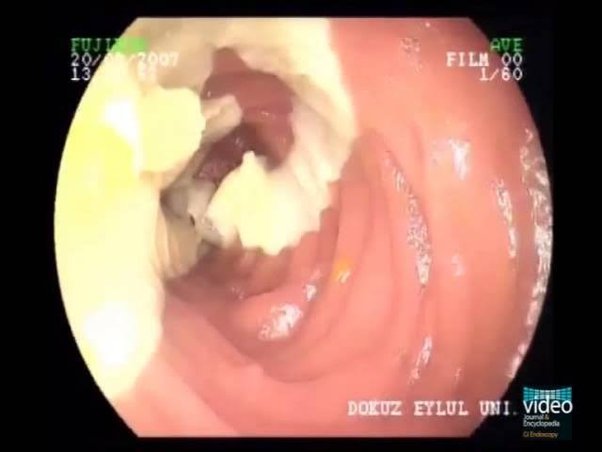

Uno de los tipos de parásitos más comunes:

Los parásitos provocan necrosis tisular, que prácticamente conduce a la amputación:

El parásito se alimenta de nuestros tejidos blandos:

Un pulmón destruido desde el interior por parásitos: